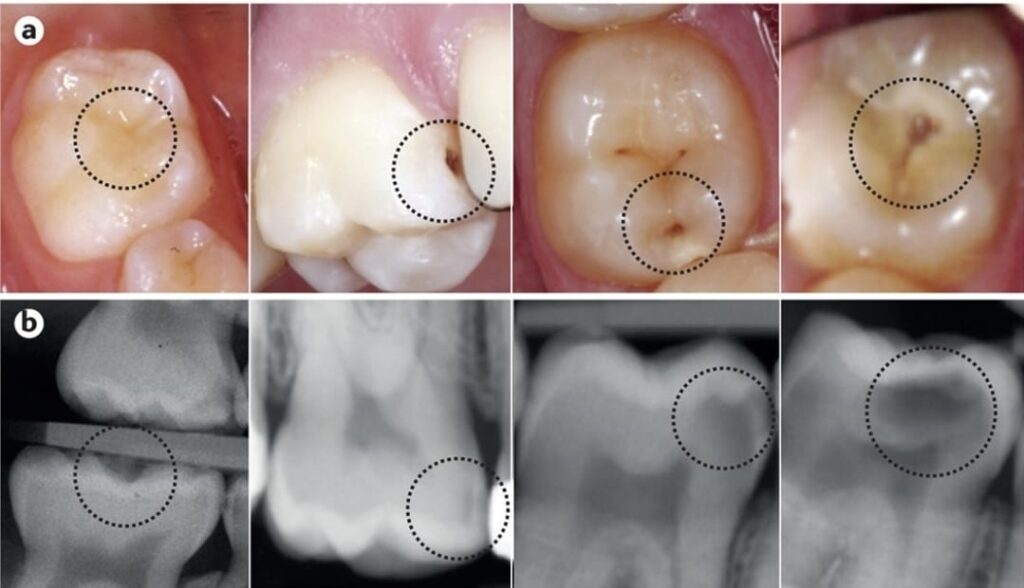

Detección temprana de caries

Las caries iniciales normalmente no producen dolor. Detectarlas a tiempo permite realizar tratamientos sencillos y conservadores, evitando procedimientos más invasivos.